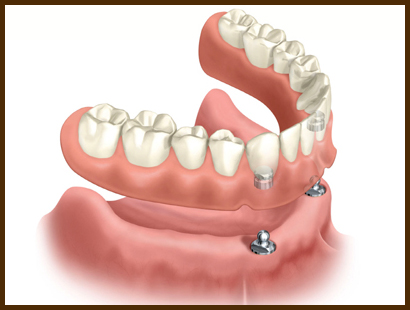

Alegand aceasta varianta a protezelor stabilizate pe implante obtinem proteze mai mici ( mult mai usor de suportat de catre pacienti), mult mai bine stabilizate (care nu mai irita gingia) si care ofera un confort superior si de ce nu, o viata noua pacientilor nostrii, permitandu-le acestora o viata sociala normala.